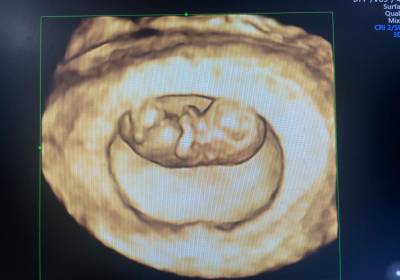

- Ultrasonography (3D & 4D)

- There is a fellowship course in fetal medicine in our department